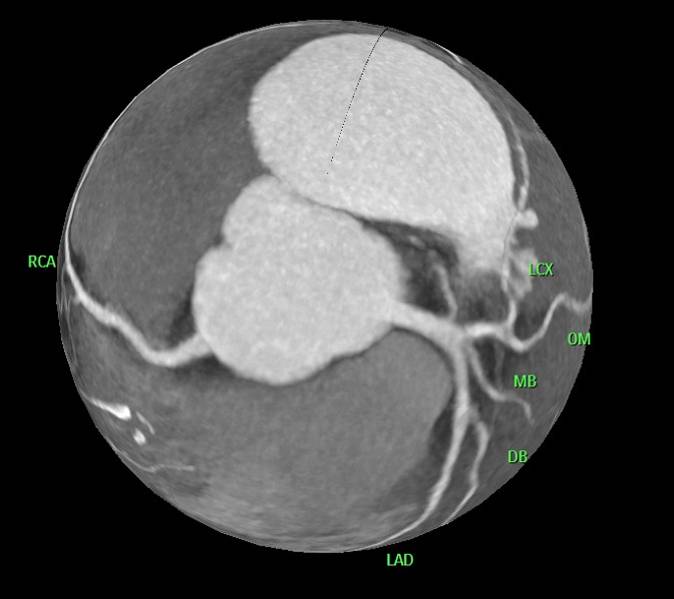

冠脉CTA

冠脉CTA提示冠脉大致正常,心脏扩大,血管密度减低。